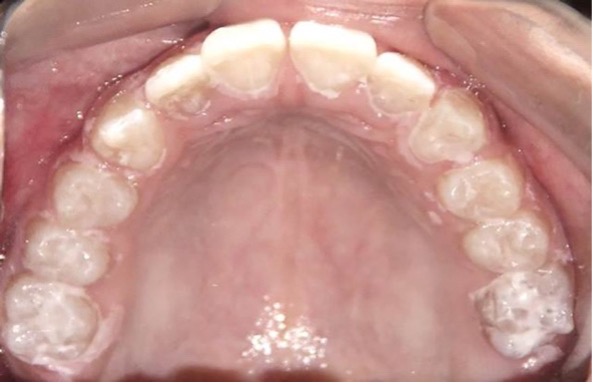

En el año 2010, el mantenedor de espacio fijo superior se descementó, pero debido a la cercana erupción de los incisivos centrales superiores permanentes obser-vada radiográficamente (Figura 5), se decidió no recementarlo, confeccionando coronas de acero independientes en los 4 molares superiores primarios (5.4, 5.5, 6.4 y 6.5) y en el 7.5, previa restauración de las lesiones de caries con ionómero vítreo (Figura 6). Cuando se observó la erupción del 4.1 y 3.1, y de los 4 molares permanentes, se realizaron 3 aplicaciones de barniz de fluoruro de sodio al 5%, cumpliendo con los protocolos establecidos.

Figura 5: Examen clínico intraoral superior, sector anterior y radiografía panorámica año 2010.

Figura 6: Postoperatorias clínicas maxilar superior e inferior año 2010.